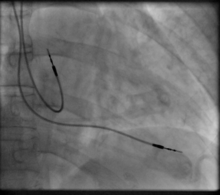

Transvenous pacing (temporary)

Transvenous pacing, when used for temporary pacing, is an alternative to transcutaneous pacing. A pacemaker wire is placed into a vein, under sterile conditions, and then passed into either the right atrium or right ventricle. The pacing wire is then connected to an external pacemaker outside the body. Transvenous pacing is often used as a bridge to permanent pacemaker placement. It can be kept in place until a permanent pacemaker is implanted or until there is no longer a need for a pacemaker and then it is removed.

Permanent pacing with an implantable pacemaker involves transvenous placement of one or more pacing electrodes within a chamber, or chambers, of the heart, while the pacemaker is implanted inside the skin under the clavicle. The procedure is performed by incision of a suitable vein into which the electrode lead is inserted and passed along the vein, through the valve of the heart, until positioned in the chamber. The procedure is facilitated by fluoroscopy which enables the physician to view the passage of the electrode lead. After satisfactory lodgement of the electrode is confirmed, the opposite end of the electrode lead is connected to the pacemaker generator.

A pacemaker is typically inserted into the patient through a simple surgery using either local anesthetic or a general anesthetic. The patient may be given a drug for relaxation before the surgery as well. An antibiotic is typically administered to prevent infection.[42] In most cases the pacemaker is inserted in the left shoulder area where an incision is made below the collar bone creating a small pocket where the pacemaker is actually housed in the patient's body. The lead or leads (the number of leads varies depending on the type of pacemaker) are fed into the heart through a large vein using a fluoroscope to monitor the progress of lead insertion. The Right Ventricular lead would be positioned away from the apex (tip) of the right ventricle and up on the interventricular septum, below the outflow tract, to prevent deterioration of the strength of the heart. The actual surgery may take about 30 to 90 minutes.